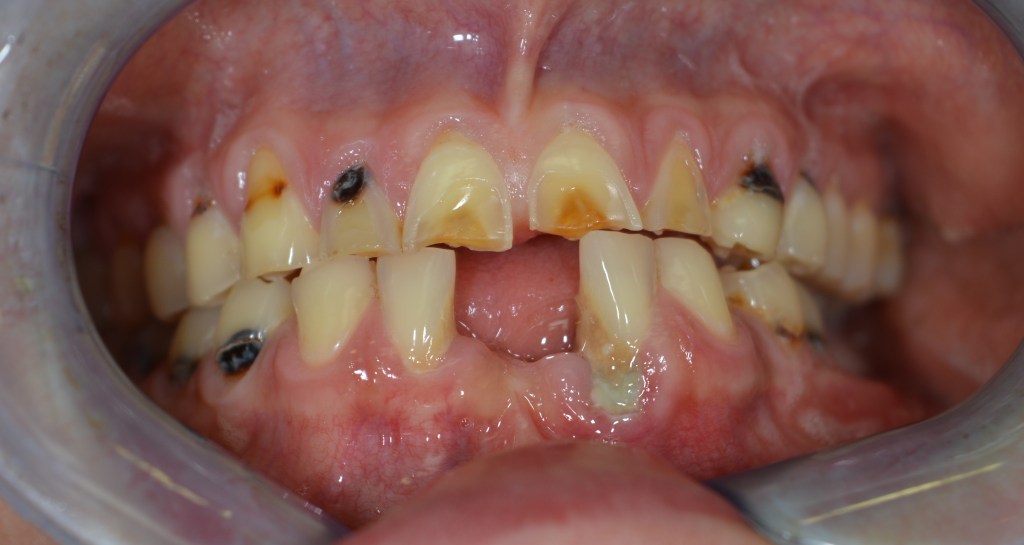

Kozmetikai és funkcionális kezelés: a kopott, elszuvasodott fogak szanálásával, hiányzó frontfogak híddal történő pótlásával, harapás megemelésével.

A választott korona típusa: CAD/CAM (komputer vezérelt tervezés/megmunkálás) technológiával készült cirkónium (fémmentes) szóló koronák, front híd.

A választott fogszín: BL 3 .

A protetikai munka elkészülésének ideje: 10 munkanap.